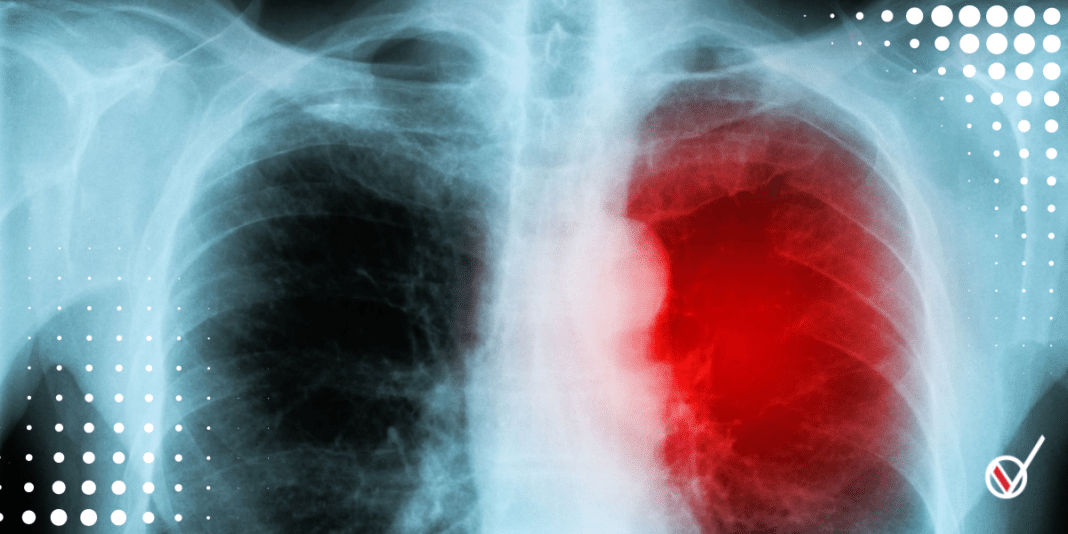

La frecuencia de los casos de miocarditis tras recibir una vacuna es, por decir lo más: mínima. Se trata de un efecto adverso bien vigilado con poquísimos casos que responden bien al tratamiento, situación que dista mucho del riesgo de miocarditis como consecuencia de una infección como COVID-19, el cual es mayor e incluye afecciones diversas.

Las notas también pasan por alto que más del 95 por ciento de los poquísimos casos de miocarditis después de la vacunación respondieron bien a las opciones de tratamiento, situación muy diferente entre quienes tuvieron complicaciones por SARS-CoV-2 como diversas afecciones cardiacas, embolias pulmonares y lesión renal aguda, por mencionar algunas.

Esta es una evaluación que realizaron los Centros para el Control y la Prevención de Enfermedades de EU encontrando que el riesgo de miocarditis después de la infección con COVID-19 es mucho mayor, ya que “los pacientes con COVID-19 entre marzo de 2020 y enero de 2021 tenían, en promedio, 15.7 veces más riesgo de miocarditis en comparación con los que no tenían COVID-19”.

Uno de sus hallazgos fue que había “entre 1 y 10 eventos adicionales de miocarditis en 1 millón de personas vacunadas con una primera o segunda dosis, pero 40 casos adicionales en 1 millón de personas infectadas con COVID-19”.

Además, señalan “mayores riesgos de pericarditis y arritmias cardíacas después de una prueba positiva de SARS-CoV-2”, asociaciones que no se observaron luego de las vacunas. Este estudio también enfatiza que “el riesgo de morbilidad y mortalidad de por vida después de la infección por SARS-CoV-2 es sustancial”.